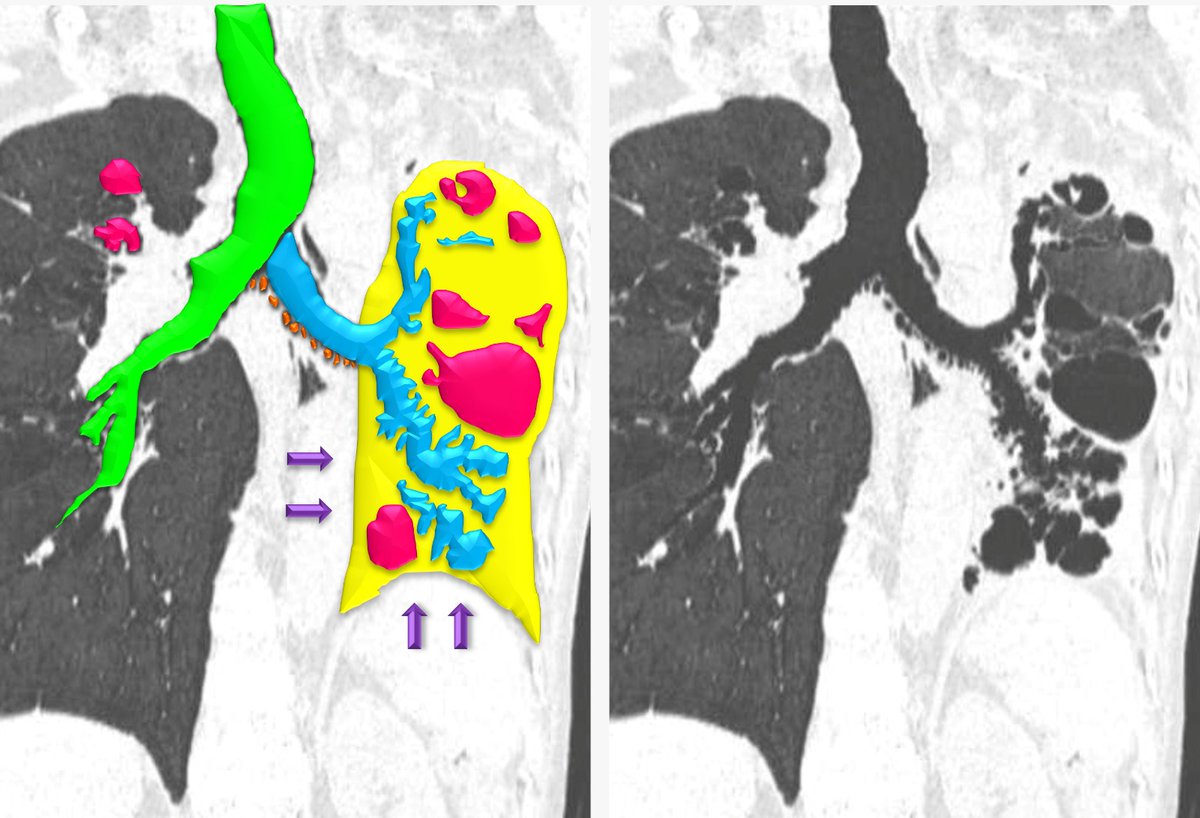

A,B CT scan of the chest, acquired during inspiration, showing

From twitter.com

Dra. Cecilia Ferrario on Twitter "47 ♀️ post TB sequelae 🫁 CT shows 🟢 Tracheal Bronchial Bronchiectasis the tracheal bronchus is a rare congenital anomaly described as a collection of bronchial variations arising from the trachea directed. tracheal/bronchial involvement may cause: bronchiectasis is an irreversible widening (dilation) of portions of the breathing tubes or airways (bronchi) resulting from damage to the airway. Bronchiectasis damages your airways, making it hard to clear mucus. more. Tracheal Bronchial Bronchiectasis.

From www.researchgate.net

A,B CT scan of the chest, acquired during inspiration, showing Tracheal Bronchial Bronchiectasis the tracheal bronchus is a rare congenital anomaly described as a collection of bronchial variations arising from the trachea directed. bronchiectasis is an irreversible widening (dilation) of portions of the breathing tubes or airways (bronchi) resulting from damage to the airway. bronchiectasis is a chronic lung disease characterized by persistent and lifelong widening of the bronchial airways. Tracheal Bronchial Bronchiectasis.